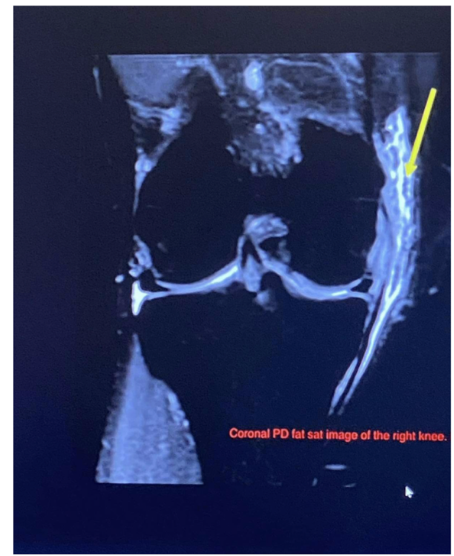

51

New cards

Pathology

• Medial collateral ligament tear

• High signal intensity within the

medial aspect of the knee indicative of fluid presence as a result of a pathological process in this case the tear.